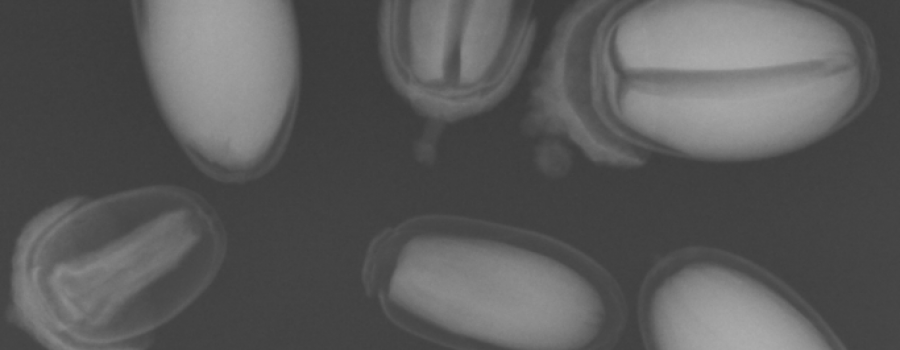

Erst das Kuscheltier - dann das Kind

Galerie der Kuscheltiere

Karl-Heinz Szeifert 28 Mar, 2019 00:00

Kinder kommen oft sehr ängstlich mit Kuscheltieren oder Puppen zum Röntgen. Um den Kindern diese Angst zu nehmen, kann man vor deren neugierigen Augen, zuerst die kuscheligen Begleiter unter die Röhre legen.